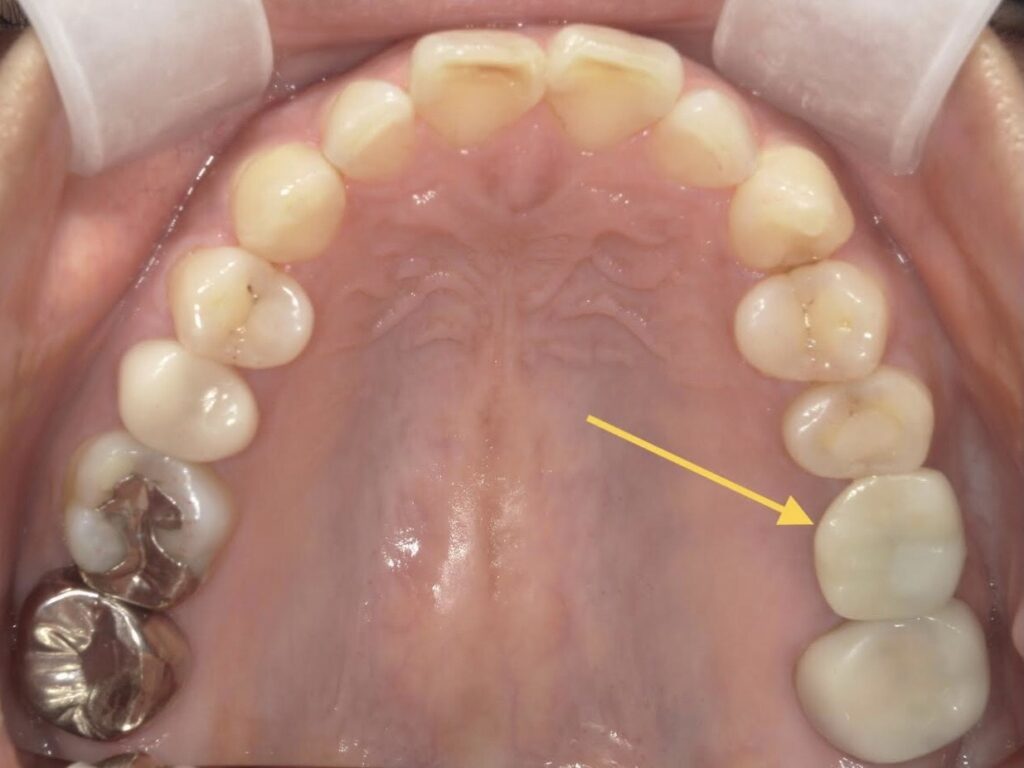

【A様】

咬合面

年齢 | 30代後半 |

性別 | 女性 |

主訴 | 歯を抜いた後、周りの歯を削ることなく噛めるようにしたい |

施術内容 | 右上第一大臼歯欠損部にインプラントを埋入し、ジルコニアクラウンを被せてあります |

治療期間 | 約1年(抜歯からジルコニアクラウン装着まで) |